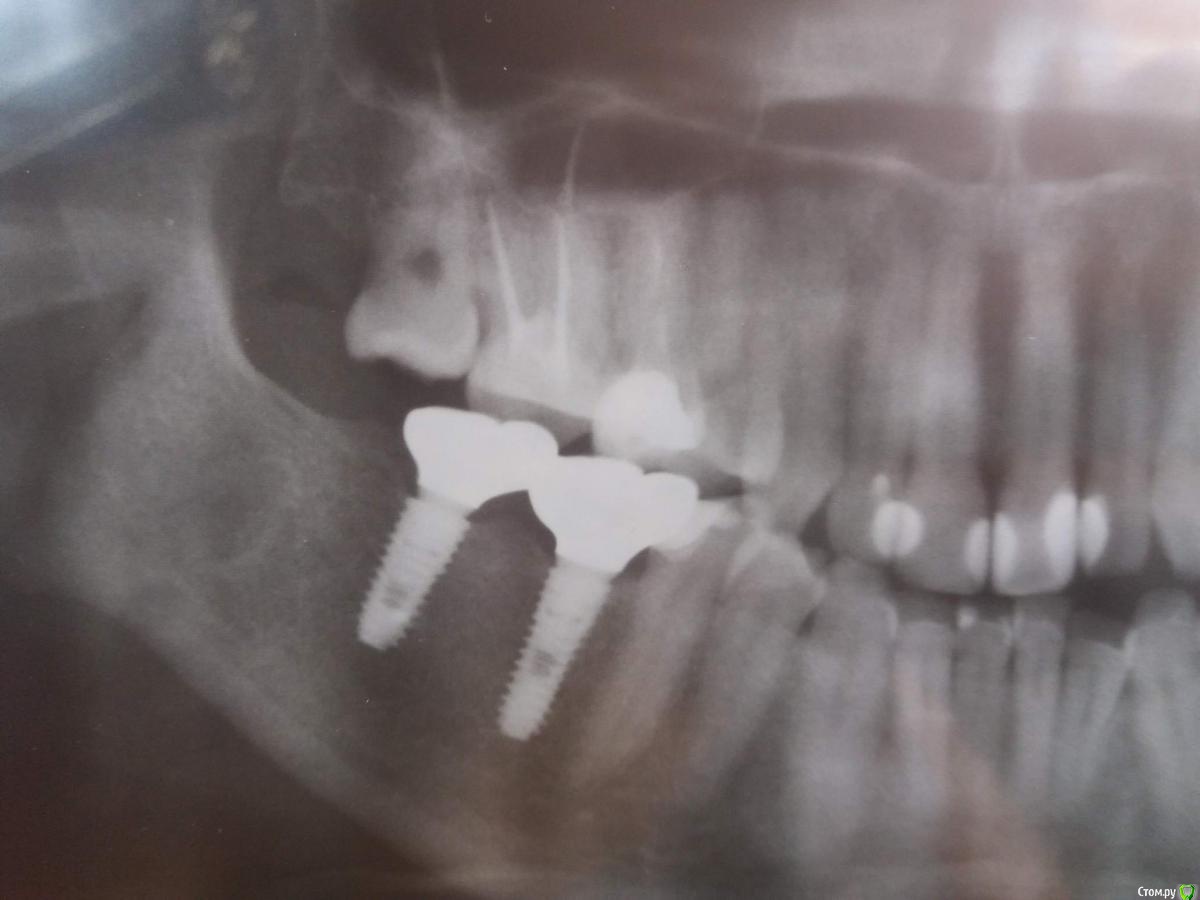

kuznetsovaev Опубликовано 19 июля, 2019 Поделиться Опубликовано 19 июля, 2019 Здравствуйте, какое исследование мне сделать чтобы сюда выложить результаты , подскажите пожалуйста. И вообще к какому врачу идти. Сегодня утром проснулась с болью справа, как будто 8 нижний зуб болит, но его давно удалили. Боли в покое нет, а при жевании даже сыра болит. Если жевать слева, не сильно открывая рот и не откусывать, то болит меньше. Жевать справа просто невозможно. В 2017г поставили мне вместо 6 и 7 нижних зубов справа импланты с пересадкой кости, а также 6 и 7 верх лево с предварительным синус-лифтингом. Может болеть имплант или что-то там за это время не хорошее образовалось... Ссылка на комментарий

kuznetsovaev Опубликовано 19 июля, 2019 Автор Поделиться Опубликовано 19 июля, 2019 Хирург говорит пейте найз. Даже на снимок не направил. Сделала ОПТГ сама. Посмотрите пожалуйста. Ссылка на комментарий